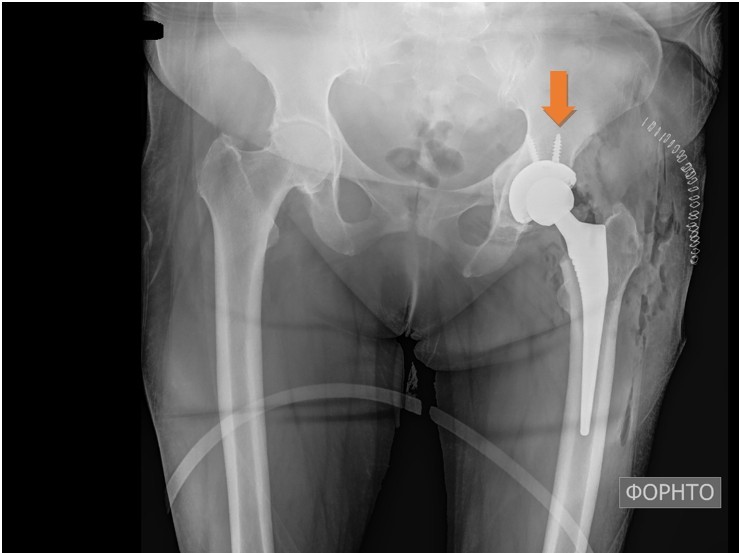

Press-fit type THA was performed on a 57-year-old patient who suffered from chronic symptoms of hip osteoarthritis (Fig. 1 and 2).

Figure 2: Post-operative X-ray of the hips. Left total hip replacement.

Although no instability or gross motion of any of the components was detected intraoperatively, the acetabular cup was fixated with two screws to reinforce the stability of the construct. The post-operative protocol comprised non-weight-bearing for the first 2 weeks, partial weight-bearing for the following weeks and initiation of full weight-bearing at 6 weeks postoperatively. At the 2-month follow-up visit the patient was able to weight bear and walk but complained of pain when rising from the seated position and during the first steps. The symptoms were improving during walking. Clinical examination revealed a leg-length discrepancy of approximately 2 cm, but the radiological evaluation showed no pathological findings. The patient was encouraged to continue rehabilitation, return to moderate daily activities, but to avoid overload. Six months postoperatively, the symptoms significantly worsened with severe pain during loading and a “snapping” feeling on every step. A thorough laboratory investigation was obtained showing no increase in inflammation markers and no other pathological findings. Further imaging with new X-rays, MRI, and CT was also inconclusive (Figs. 3, 4, 5).

Figure 3: No periprosthetic lucencies at the 6-month post-operative X-ray.